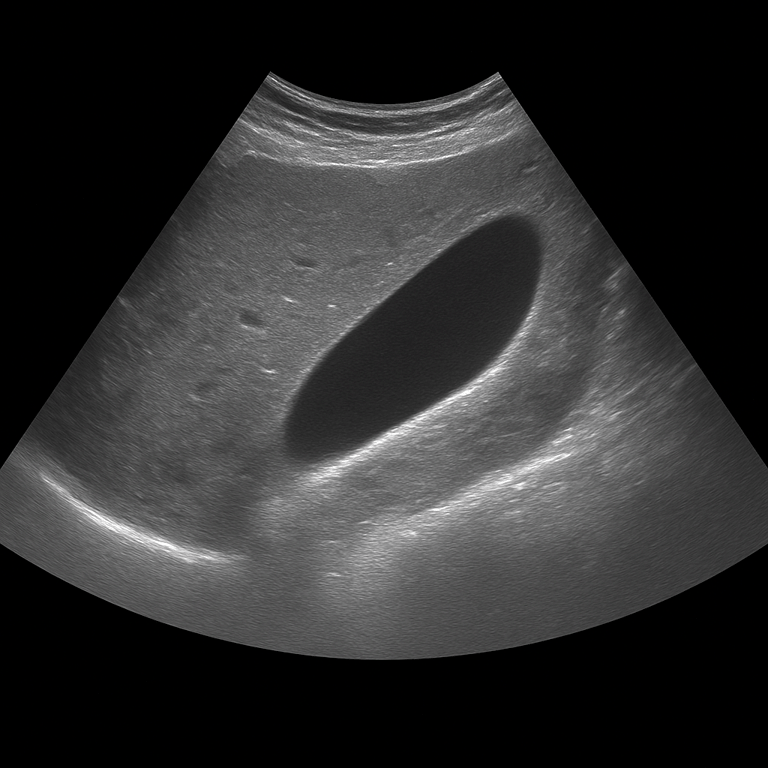

A gallbladder ultrasound is used to examine the gallbladder wall, contents and function. The examination is performed by a specialist in radiology and provides detailed real-time images that show whether the gallbladder contains stones, fluid or signs of inflammation. Gallbladder ultrasound is used as the first-line method when gallstone disease or inflammation of the gallbladder (cholecystitis) is suspected.

A gallbladder ultrasound is recommended for pain under the right rib cage, nausea, bloating or recurrent discomfort after eating fatty foods. The examination can show whether the gallbladder contains stones, sludge (biliary gravel) or a thickened wall that indicates inflammation. It is also used to follow up on previous gallstone problems or after surgery where parts of the biliary system remain.

The examination is performed while you lie on your back or slightly on your left side. A gel is applied to the skin and the doctor moves the ultrasound probe over the area under the right rib cage. The examination usually takes 10–20 minutes. For the best image quality, you need to fast for at least 4–6 hours beforehand, as an empty gallbladder is difficult to assess.